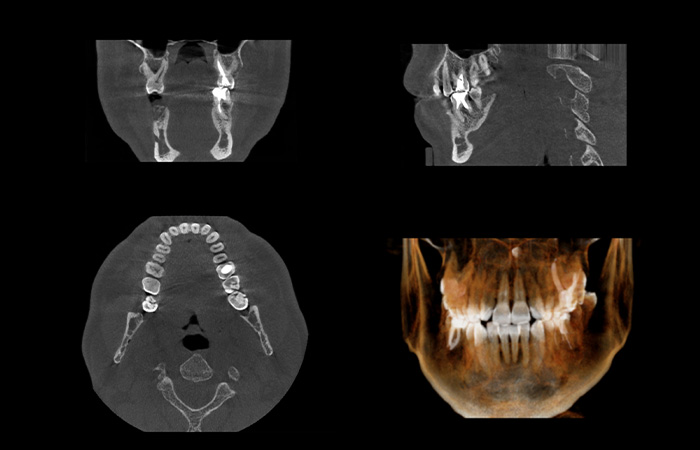

・口腔内診査(歯並び・かみ合わせ・顎の状態の確認)

・パノラマレントゲン撮影

これらの検査をもとに、お口の状態や適応を確認したうえで治療を進めていきます。

その後、検査データと気道解析結果をもとに、治療効果を予測した上で治療計画を立てます。患者さまにも画像をお見せながら、気道の状態をわかりやすくご説明いたします。

より精密な製作のために

以前は下顎の位置を感覚的に決めて製作することが多く、気道が十分に開かない場合は再製作が必要でした。当院では、CT解析で気道の開き具合を事前に確認し、適切な位置を設計段階で決定します。